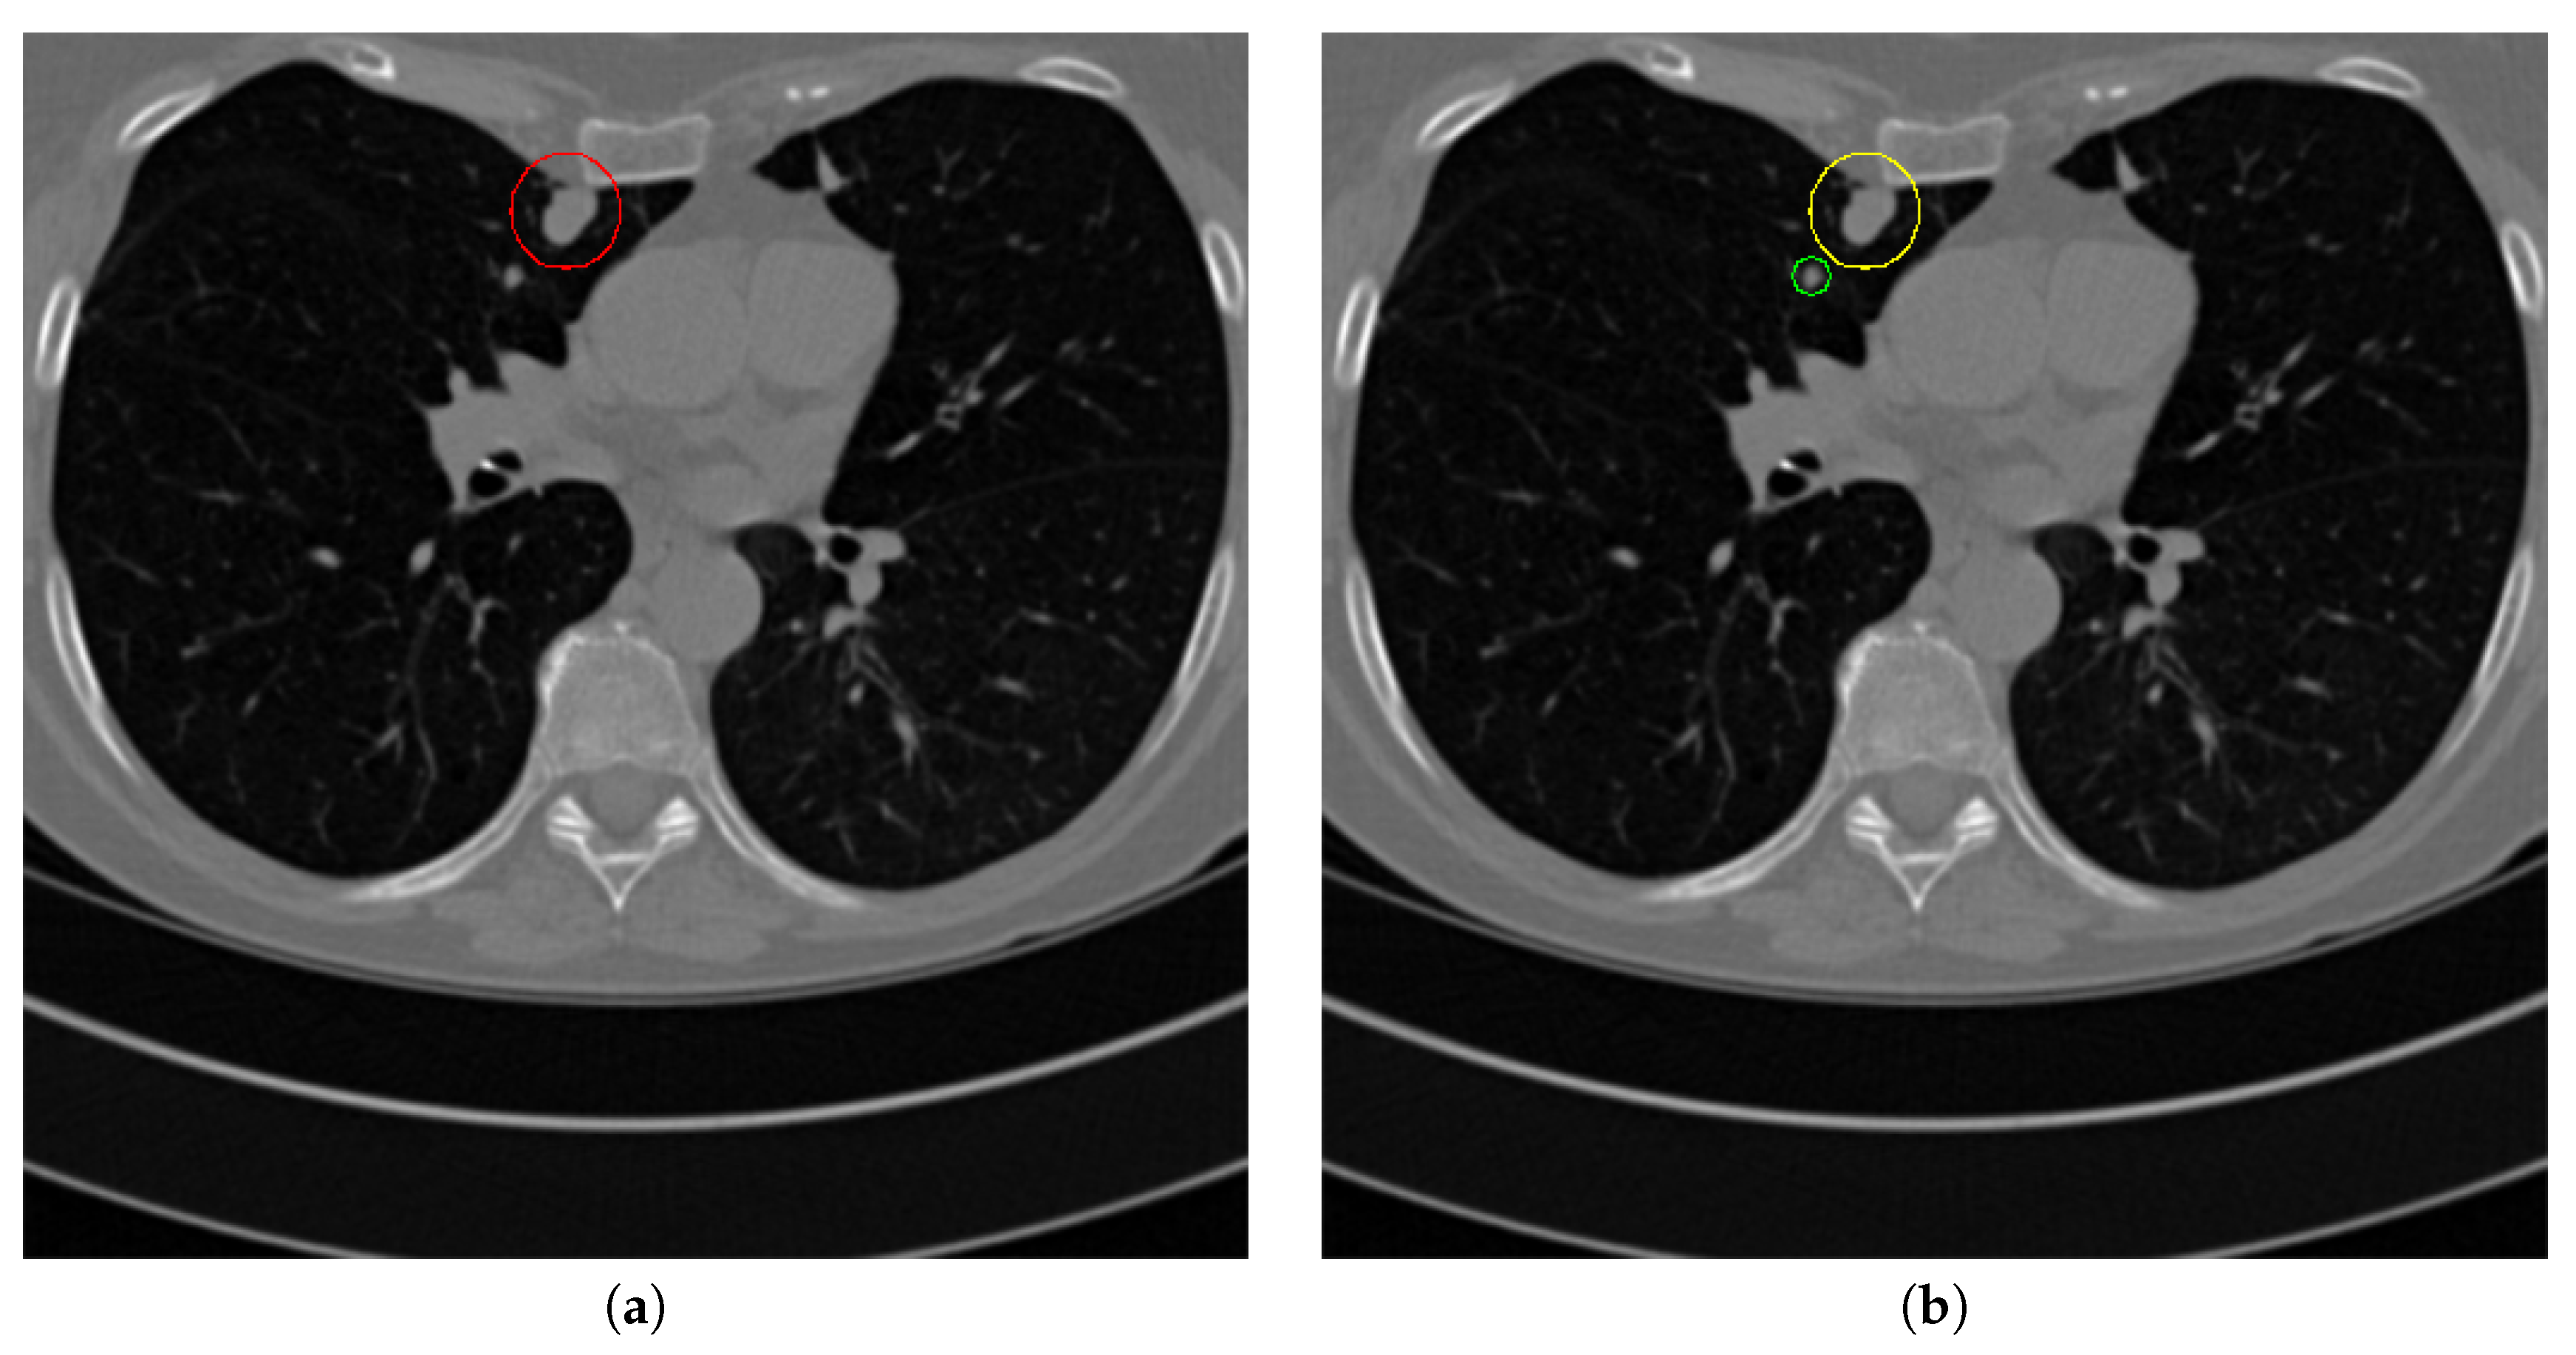

Figure 17 and Figure 18 illustrates the performance of pulmonary nodule detection by different methods on two example images in the LUNA16 dataset. In addition, Figure 19 and Figure 20 illustrates the performance of pulmonary nodule detection by different methods on two examples images in the TianChi dataset. As marked by green circles in Figure 18b,c and Figure 19c, the 3D-FCN and MR-CNN directly detected the nodule candidates from the original CT image without pre-processing, resulting in the incorrect determination of non-nodule tissue outside lung as nodule since the outside-lung organs are not filtered out from the nodule candidates. The 3D-UNET and PRN-HSN add the lung parenchyma region segmentation stage before detecting the nodule candidates inside-lung, so they provide better performance than 3D-FCN and MR-CNN in decreasing the over-estimation rate. However, they still suffer from unsatisfactory results for the following reasons: (1) the lung parenchyma segmentation is generated by simple thresholding with morphological operations so the near-edge regions are lost, shown as the one marked by yellow circle in Figure 20d,e; (2) the convolution kernel used in nodule candidate detection of 3D-UNET is with a small receptive field to learn global features from the image, so it is likely to confuse some small tissues as true nodules with small sizes, shown as the one marked by green circle in Figure 18d and Figure 20d; and (3) the proposed hierarchical saliency network (HSN) in PRN-HSN for nodule candidate classification omits the information with different resolutions, resulting in that the small-size nodule within the weakened, low-resolution region cannot be correctly recognized, as shown by the yellow circle in Figure 18e. The DCNN method simply applies the Faster RCNN method to provide good performance with low computational cost, but it may omit the nodules on the parenchymal edge shown as yellow circles in Figure 20f. CLAHE-SVM method adds a contrast-enhancement pre-processing before the nodule detection, leads to better performance on detecting nodules in the low-contrast region. However, it is easily to over-enhance the small-size tissues and over-estimate them as nodules, as shown by the green circles in Figure 19g andFigure 20g. The detection is also implemented over the whole image, so the nodule on the parenchyma edge may be under-estimated show by the yellow circle in Figure 20g. The Mask-RCNN method provides better effects than the above methods because of the good performance of Mask-RCNN in object detection. However, the performance is not stable for the small-size tissues and the irregular-shape nodule, shown by the green circles in Figure 17h and Figure 19h, and the yellow circle in Figure 19h. The proposed method takes the advantage of a series of U-Net-like networks to perform the nodule detection following a “coarse-to-fine” order of inside-lung region detection, nodule candidate detection and nodule determination. The U-Net network is modified by embedding inception structure, replacing the convolution and pooling by dilated convolution, and adapting multi-scale pooling and multi-resolution convolution connection, for different requirements of the three stages, respectively. Moreover, it makes use of the MSE loss, VGG-19-based perceptual loss as the complement of dice loss to optimize the whole framework. Therefore, as shown in Figure 17i, Figure 18i, Figure 19i and Figure 20i, the proposed framework provides superior performance on pulmonary nodule detection with low over-estimation of non-nodule tissues at the same time.

Figure 18. The result of detecting pulmonary nodules by different methods on another example image in LUNA16 dataset. Red circle represents the ground truth region of nodules, blue circles represent the correct estimation of pulmonary nodules, green circles represent the over-detected nodules, while yellow circles denote the nodules being omitted. (ai) are: ground truth nodule in the given chest CT image, nodule detected by 3D-FCN, MR-CNN, 3D-UNET, PRN-HSN, DCNN, CLAHE-SVM, MASK-RCNN and our proposed method.